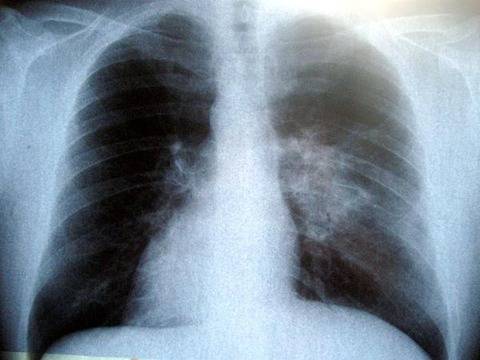

От Министерство на здравеопазването обявиха, че в лечебните заведения за диагностика и лечение на туберкулоза стартират безплатни прегледи за туберкулоза от 19 до 23 юни 2017 г „Дни на Отворени врати”. Списък на лечебните заведения с адреси – вижте по-долу.

Тази инициатива се осъществява по Програма „Подобряване на устойчивостта на Националната програма по туберкулоза”. Програмата е към Министерство на здравеопазването, финансирана от Глобалния фонд за борба срещу СПИН, туберкулоза и малария.